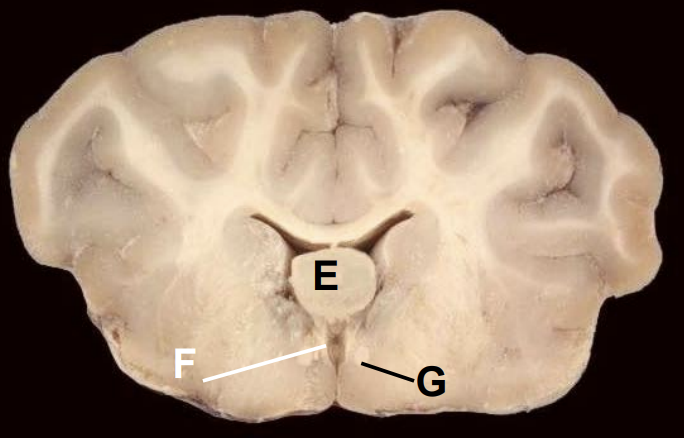

E

Thalamus

Q

Third ventricle

G

Fornix